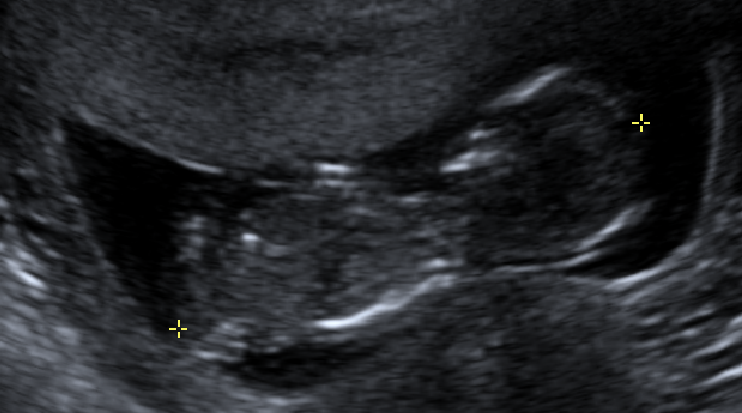

Would anyone like to take a guess at the gender? The attached photos were taken 13 weeks, 2 days. These are the best pics I have:

Attachment 25572Attachment 25573